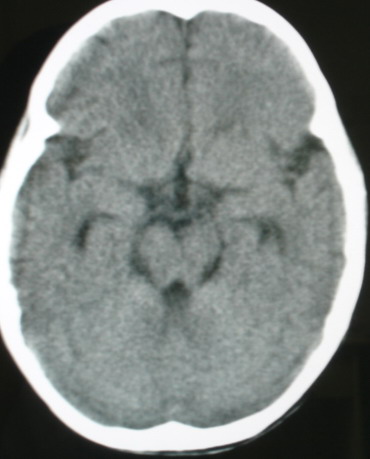

m/8y/,右侧眼睑下垂数日,发育良好,无外伤史,无头痛、恶心、呕吐,学习成绩良好。

ct意见:1、颅内血管畸形。2、右侧海绵窦血管瘤(颈内动脉海绵窦段动脉瘤)。3、脑萎缩。4、建议mr或dsa.

增强片

海绵窦瘘.注意眶内静脉有扩张.

右侧海绵窦血管瘤伴右侧海绵窦漏形成(由于右眼上静脉较左侧增粗。故考虑)。

支持 右侧颈内动脉海绵窦瘘.注意眶内静脉有扩张.